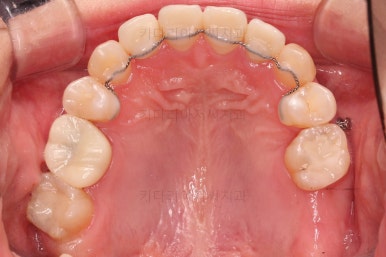

치열은 매우 가지런해졌고요.

추후에 발치 공간을 모아나가야 합니다.

윗니 앞니는 급한대로 신경치료 부터 진행했고, 최종 심미보철은 교정 후 미루었습니다.

공간을 줄여나가고 순차적으로 충치치료도 마무리 해갑니다.

마무리 못한 어금니 치료와 앞니 심미보철을 마무리 합니다.

앞니 심미보철까지 마무리 되었습니다.